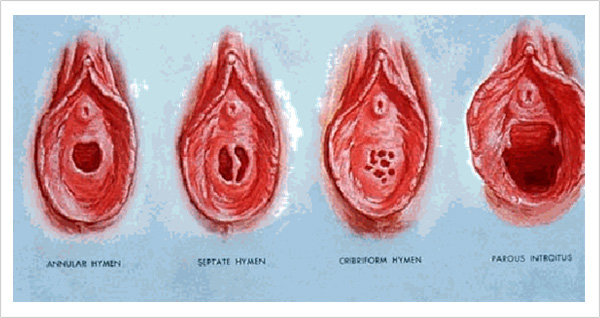

20~30���� ���� �������� ��ȥ�̶�� �λ����� ���� �߿��� ��ȯ���� �½��ϴ�. �ӽŰ�, ��� ��ӴϷμ� �ڳ��� ������ �Ƴ��μ��� ���� ������ �ϰ� �Ǵ°� �Ϲ����Դϴ�. ���� ��ȥ������ �̷� ������ ���� �߿伺�� ����� �ν����� ���Ͽ� ��ĩ�ϸ� �ǰ��� ���ؼ� ��Ȧ�ϱ� �����ϴ�. ���� ��ȥ�� �յ� ���� �������� ��ȥ �� �ǰ������� �ݵ�� �°��� �����ϴ�.